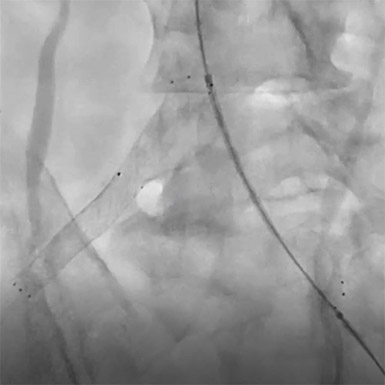

PTAからワイヤーを18Gの針で穿刺し【図5】、プルスルーを実施。【図6】高度石灰化のため、プルスルーしたワイヤーを使用して穿刺針でプリパレーションを行い、4Frマイクロパンクチャーシースを挿入しPTA閉塞部をCrosperioRX 2.5-200mmで拡張しPTAの開存を確認。【図7】

治療を行ったPTAより、ラジフォーカスガイドワイヤーM スティッフJタイプを挿入し、5FrガイディングシースでSFAへアプローチ。ガイディングシース内にガイディングカテーテルを挿入し、0.014inchテーパーワイヤー 45gをエコーガイド下で穿通させCrosstellaOTW 3.0-40mmを拡張しながら進めた。【図8】 Crosstella OTWバルーンを通し、0.014inch 300㎝のワイヤーに交換。IVUSはAnteOwl WRを使用しワイヤールートを確認したところすべてTrue Lumenであることを確認。要所で石灰化が厳しい部分があったため、カッティングバルーンを使用し拡張。